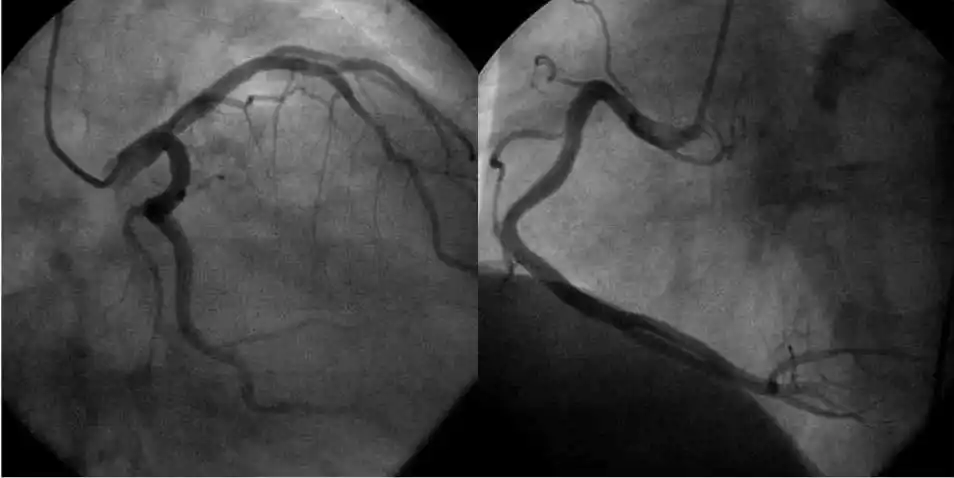

心脏循环有没有狭窄,下面这张图是一个有糖尿病,高血压的患者做的造影

冠心病血管造影图像